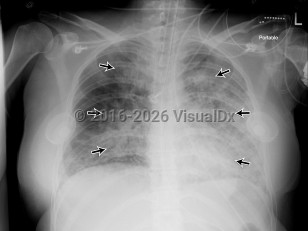

Congestive heart failureCongestive heart failure

Acute respiratory distress syndromeAcute respiratory distress syndrome